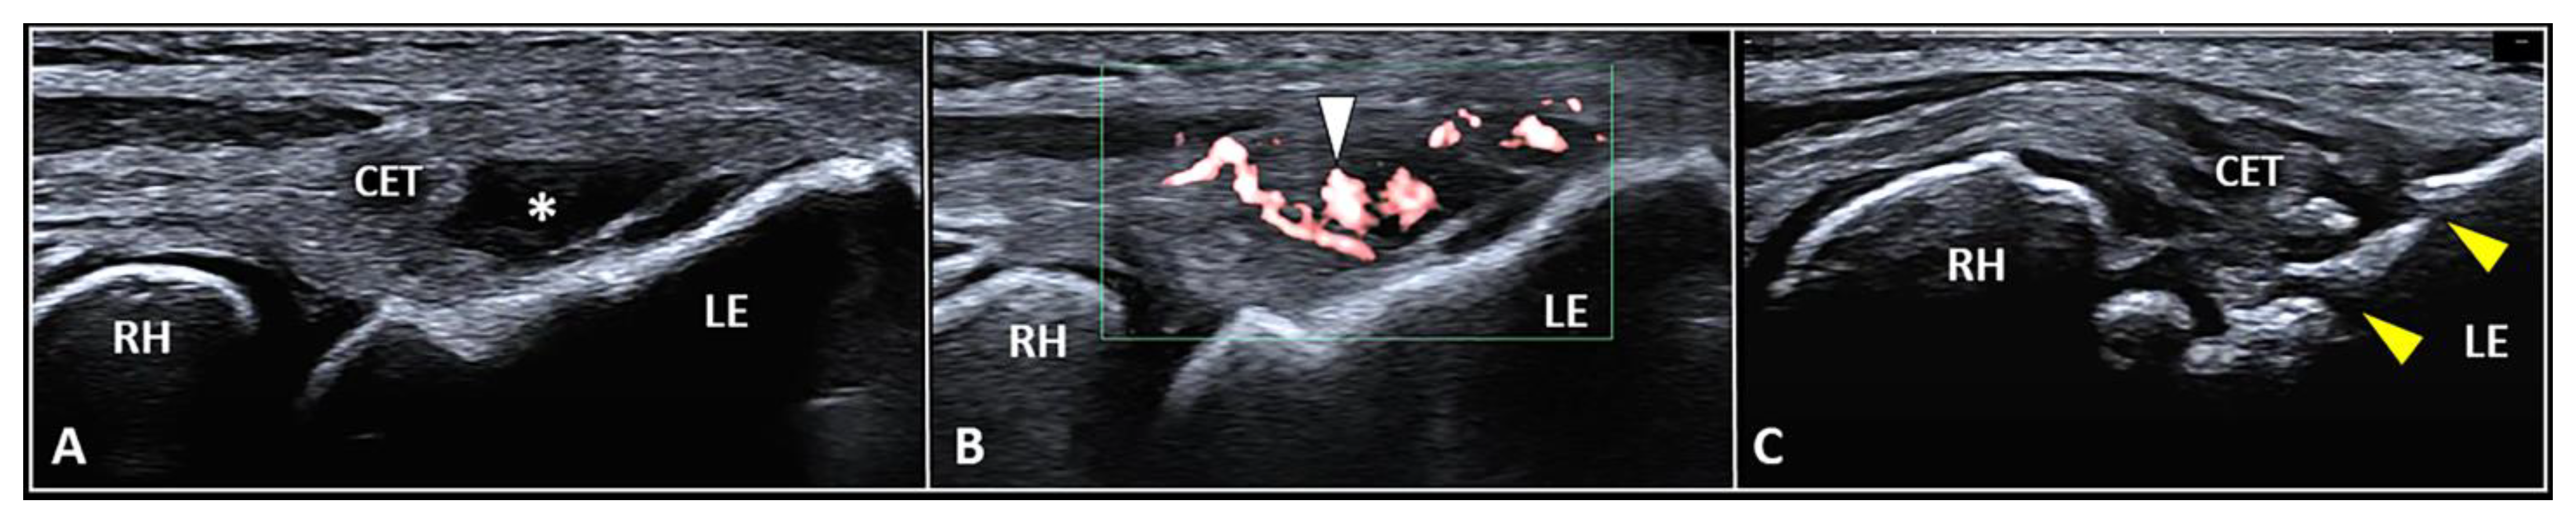

3.2. Intratendinous Injection

| Intratendinous | Inside a specific portion of the CET | Intralesional injection and/or fenestration of the degenerated area |